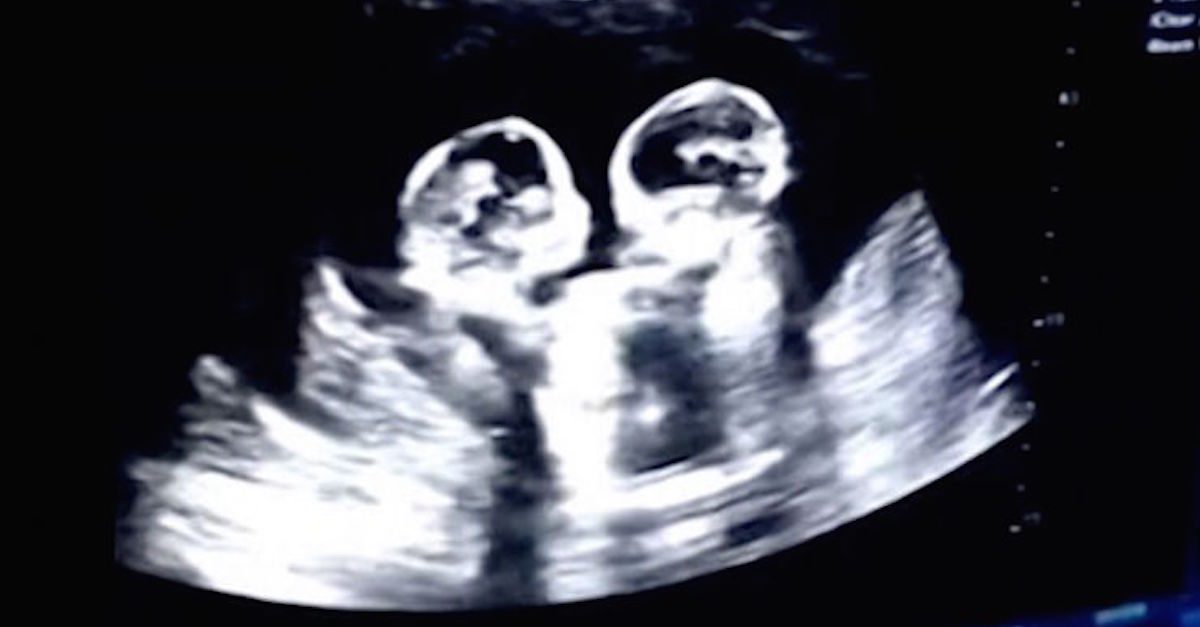

Identical Twin Sisters Spotted ‘Fighting’ in Mom’s Womb During Ultrasound

Mrs. Tao was four months pregnant with identical twins when she was accompanied by Mr. Tao to a prenatal check-up. It is very common for unborn twins to interact in the womb, and Mr. Tao had witnessed them interacting before. But this time, it was something very different.

Cherry and Strawberry, the twins were nicknamed after their mother’s favorite fruits. Their pregnancy was known as monochorionic-monoamniotic twin pregnancy where they shared the same amniotic sac and placenta. Also called the ‘Mo-Mo’ twins, it posed one of the highest types of risks involved with twin pregnancies.

Mr. Tao had often seen one of the twins cuddling up against the other. But this time, it was completely different. During the amniotic fluid tests, Mr. Tao witnessed the twins boxing with each other for a few rounds. They were kicking and punching each other from within their mother’s womb. Mr. Tao was happy to be there during the amniotic fluid tests and to witness this event.